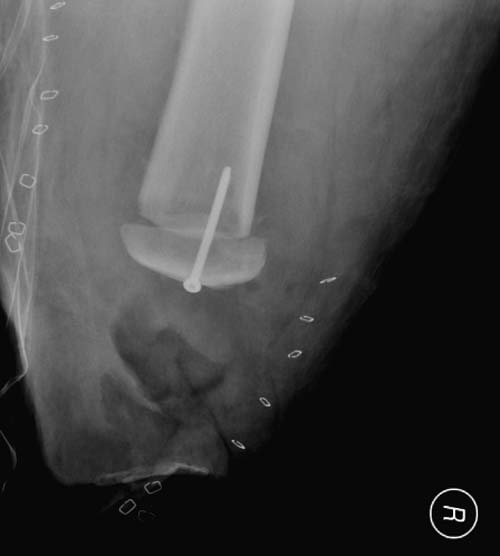

Здесь снимки, которые показывают направление стержня, а также идею

репозиции вытяжением. На рентгенопроницаемых столах имеется возможность

установить дополнительную раму, где по желанию можно увеличить или

уменьшить высоту угла вытяжения. Для репозиции таза больной в положение

на спине, стержень для вытяжения остается во время операции. Система

подойдет для тракции головки бедра из вертлужной впадины, и для этого

стерильная веревка и Synthes Universal Chuck with T-Handle.

Двухстороннее повреждение крестца и травматическая ампутация бедра, где

неопытной бригадой дежурантов установлен верхний наружный фиксатор для

стабилизации. На третий день ревизия на более стабильный, и

окончательная фиксация. Первые снимки после стабилизации таза, и другие,

где показаны (параллельные) правильная установка на AIIS т.е на месте

прикрепления прямой мышцы бедра. Ампутация закончена костно пластическим

методом.